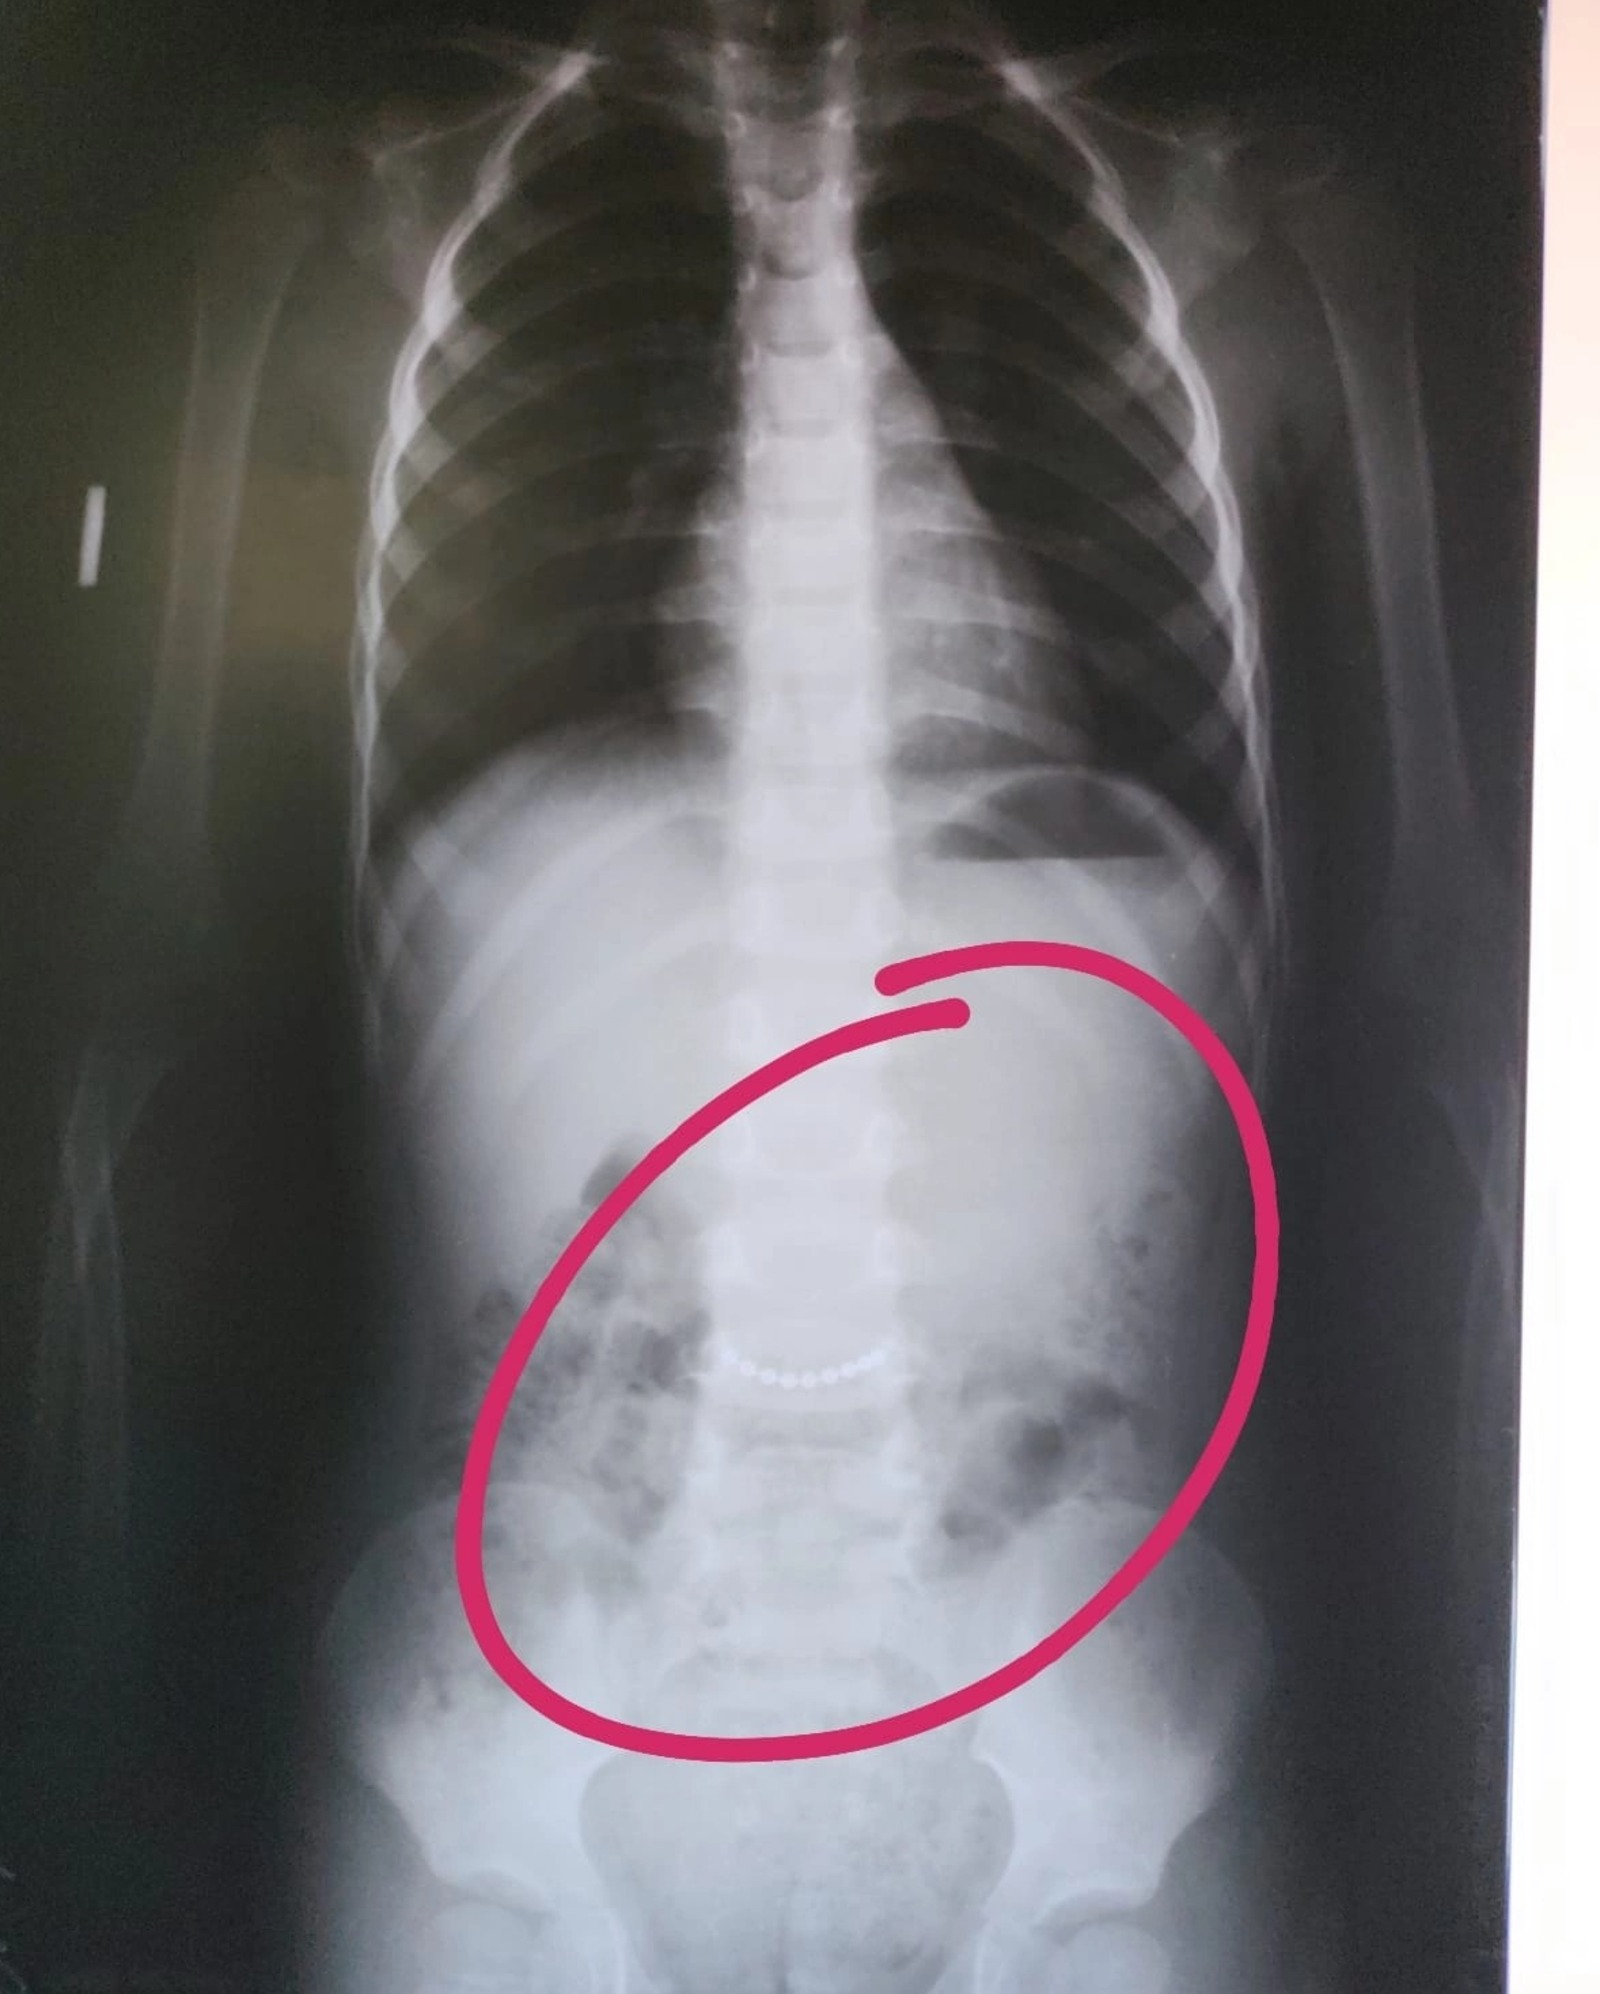

В Башкирии медики обнаружили в животе трехлетнего ребенка цепочку. Пациент с подозрением на инородное тело в брюшной полости поступил в центральную районную больницу в селе Раевский.

Рентген подтвердил наличие металлического предмета. Как оказалось, это была цепочка. К счастью, она покинула детский организм, не успев нанести серьёзный вред.